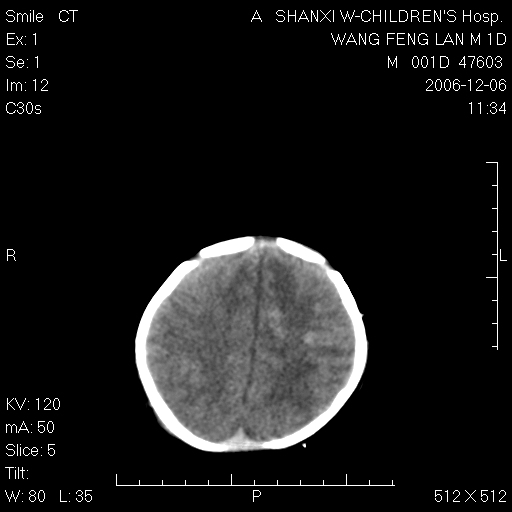

以下是引用zjzjr在2006-12-6 19:29:00的发言:[br]支持新生儿缺血缺氧性脑病伴少量蛛网膜下腔出血.

以下是引用卜一在2006-12-6 21:38:00的发言:[br][br] 支持:新生儿缺血缺氧性脑病伴少量蛛网膜下腔出血 [br]